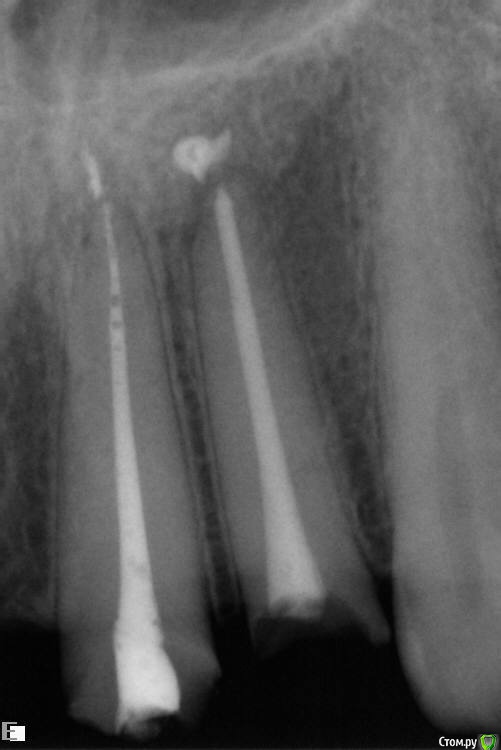

Rashid077 Опубликовано 7 января, 2015 Поделиться Опубликовано 7 января, 2015 (изменено) Здравствуйте. Чем вы вынимаете отломки из каналов если не секрет? втор сним случайн Изменено 7 января, 2015 пользователем Rashid077 Ссылка на комментарий

Rashid077 Опубликовано 7 января, 2015 Поделиться Опубликовано 7 января, 2015 Помогите пожалуйста) есть ли возможность вынуть отломок, 46зуб, файл реципрок 25, зуб ранее был лечен, раскрыт 3 канала 2 нед кальций, при повторной обработке произошел отлом) как быть? Ссылка на комментарий

Slaggy Опубликовано 8 января, 2015 Поделиться Опубликовано 8 января, 2015 (изменено) Помогите пожалуйста) есть ли возможность вынуть отломок, 46зуб, файл реципрок 25, зуб ранее был лечен, раскрыт 3 канала 2 нед кальций, при повторной обработке произошел отлом) как быть? А н как не вынуть. Либо вместе сзубом,либо паковать Да вроде обошли, ничего так - тройку циклов хлорки-лимонки и может сам всплыть. Бывает.Все зависит от того, с каким усилием его в канал пихали. Если без усилия работали - всплывет.С ультразвуком, конечно. Ы.У меня за соседним креслом доктор когда работает - торк как фрикцион на спининге трещит. Ну, думаю, опять крупняка подняла... Изменено 8 января, 2015 пользователем Slaggy 1 Ссылка на комментарий

Slaggy Опубликовано 10 января, 2015 Поделиться Опубликовано 10 января, 2015 Уз работать по стандартному протоколу, как и всегда. 3Х20 секунд "свободным" файлом не ближе 1-2 мм от WL на минимальной мощности.Если удалось обойти инструмент, есть шанс что он вымоется колебаниями создаваемыми ультразвуком. Вообще, в случае отлома эндоинструмента делаю байпасс 15 к-файлом, а потом по этой дорожке вкручиваю хенстрем и выдергиваю, вкручиваю и выдергиваю - до 25-35 диаметра. Потом мою по протоколу.Если не потянется за н-файлом и не вымоется озвучкой - пакуем и меняем прогноз на (((. Гипохлораном не работал. Лимонка есть во всех продуктовых магазинах. Ссылка на комментарий